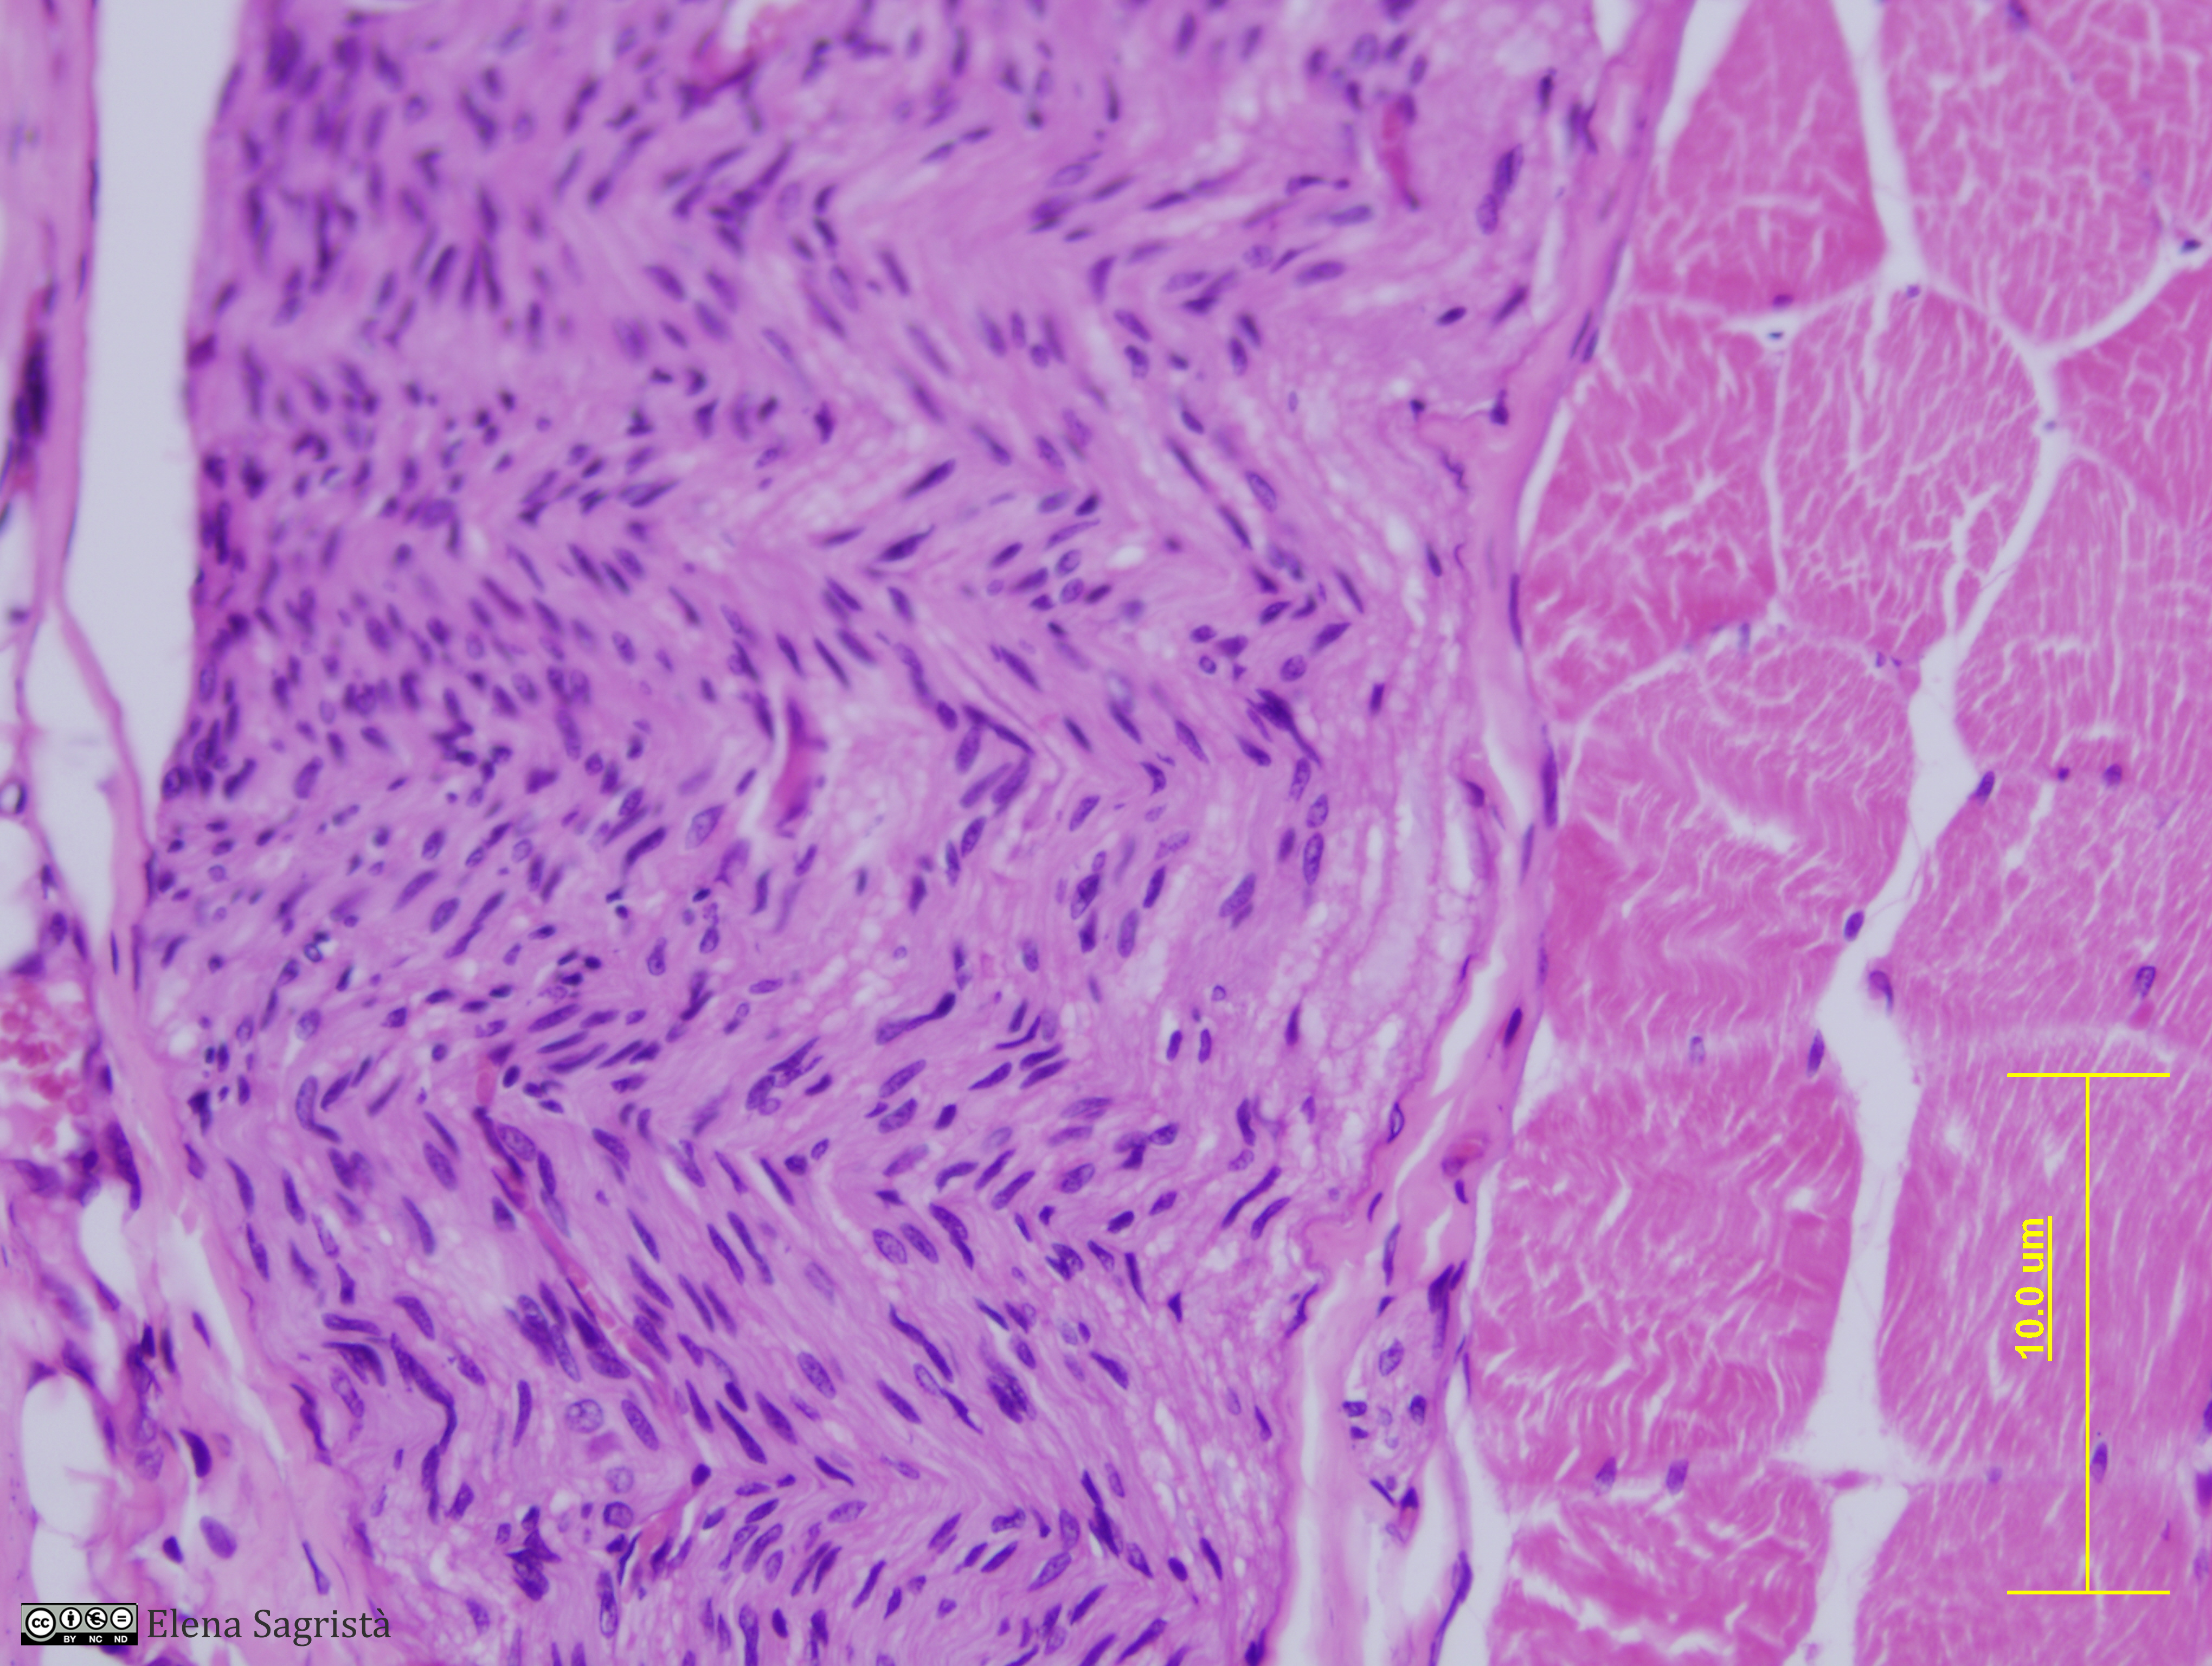

Histologia imatges: 09 Teixit nerviós perifèric

Imatges de preparacions histològiques de Teixit nerviós perifèric. Microscopia òptica.